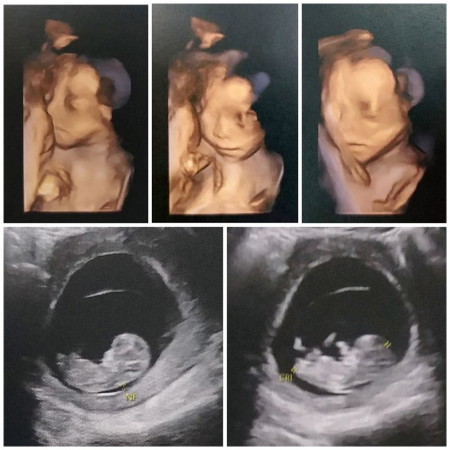

5 เดือน แร้ววววค่า

4 มิติ ใช่ไหมคะคุณแม่

4มิติชัดมากเลยค่ะ